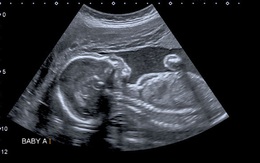

Lần đầu tiên tìm thấy các hạt ‘bồ hóng’ trong cơ thể thai nhi

TTO - Một nghiên cứu mới ở Bỉ cho thấy các "hạt carbon đen", còn gọi là "hạt nano bồ hóng" ô nhiễm trong không khí, đã thấm vào cơ thể của các thai nhi. Điều này có thể làm các thai nhi chậm phát triển hoặc tử vong.